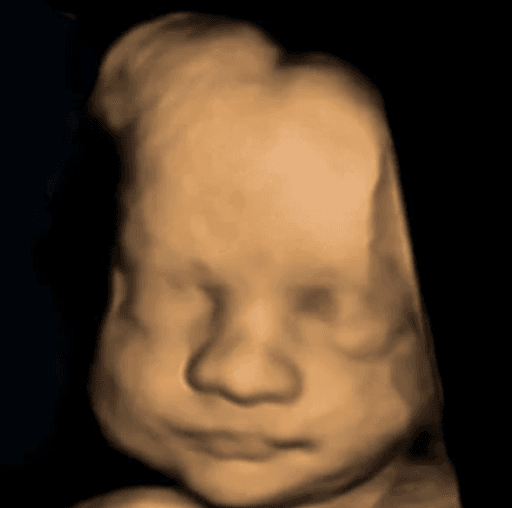

See babies, before & after

Your baby

See your baby smile in 2 minutes.

Your 3D ultrasounds stay private. Images here are shown with permission — yours will never appear on this page without your consent.